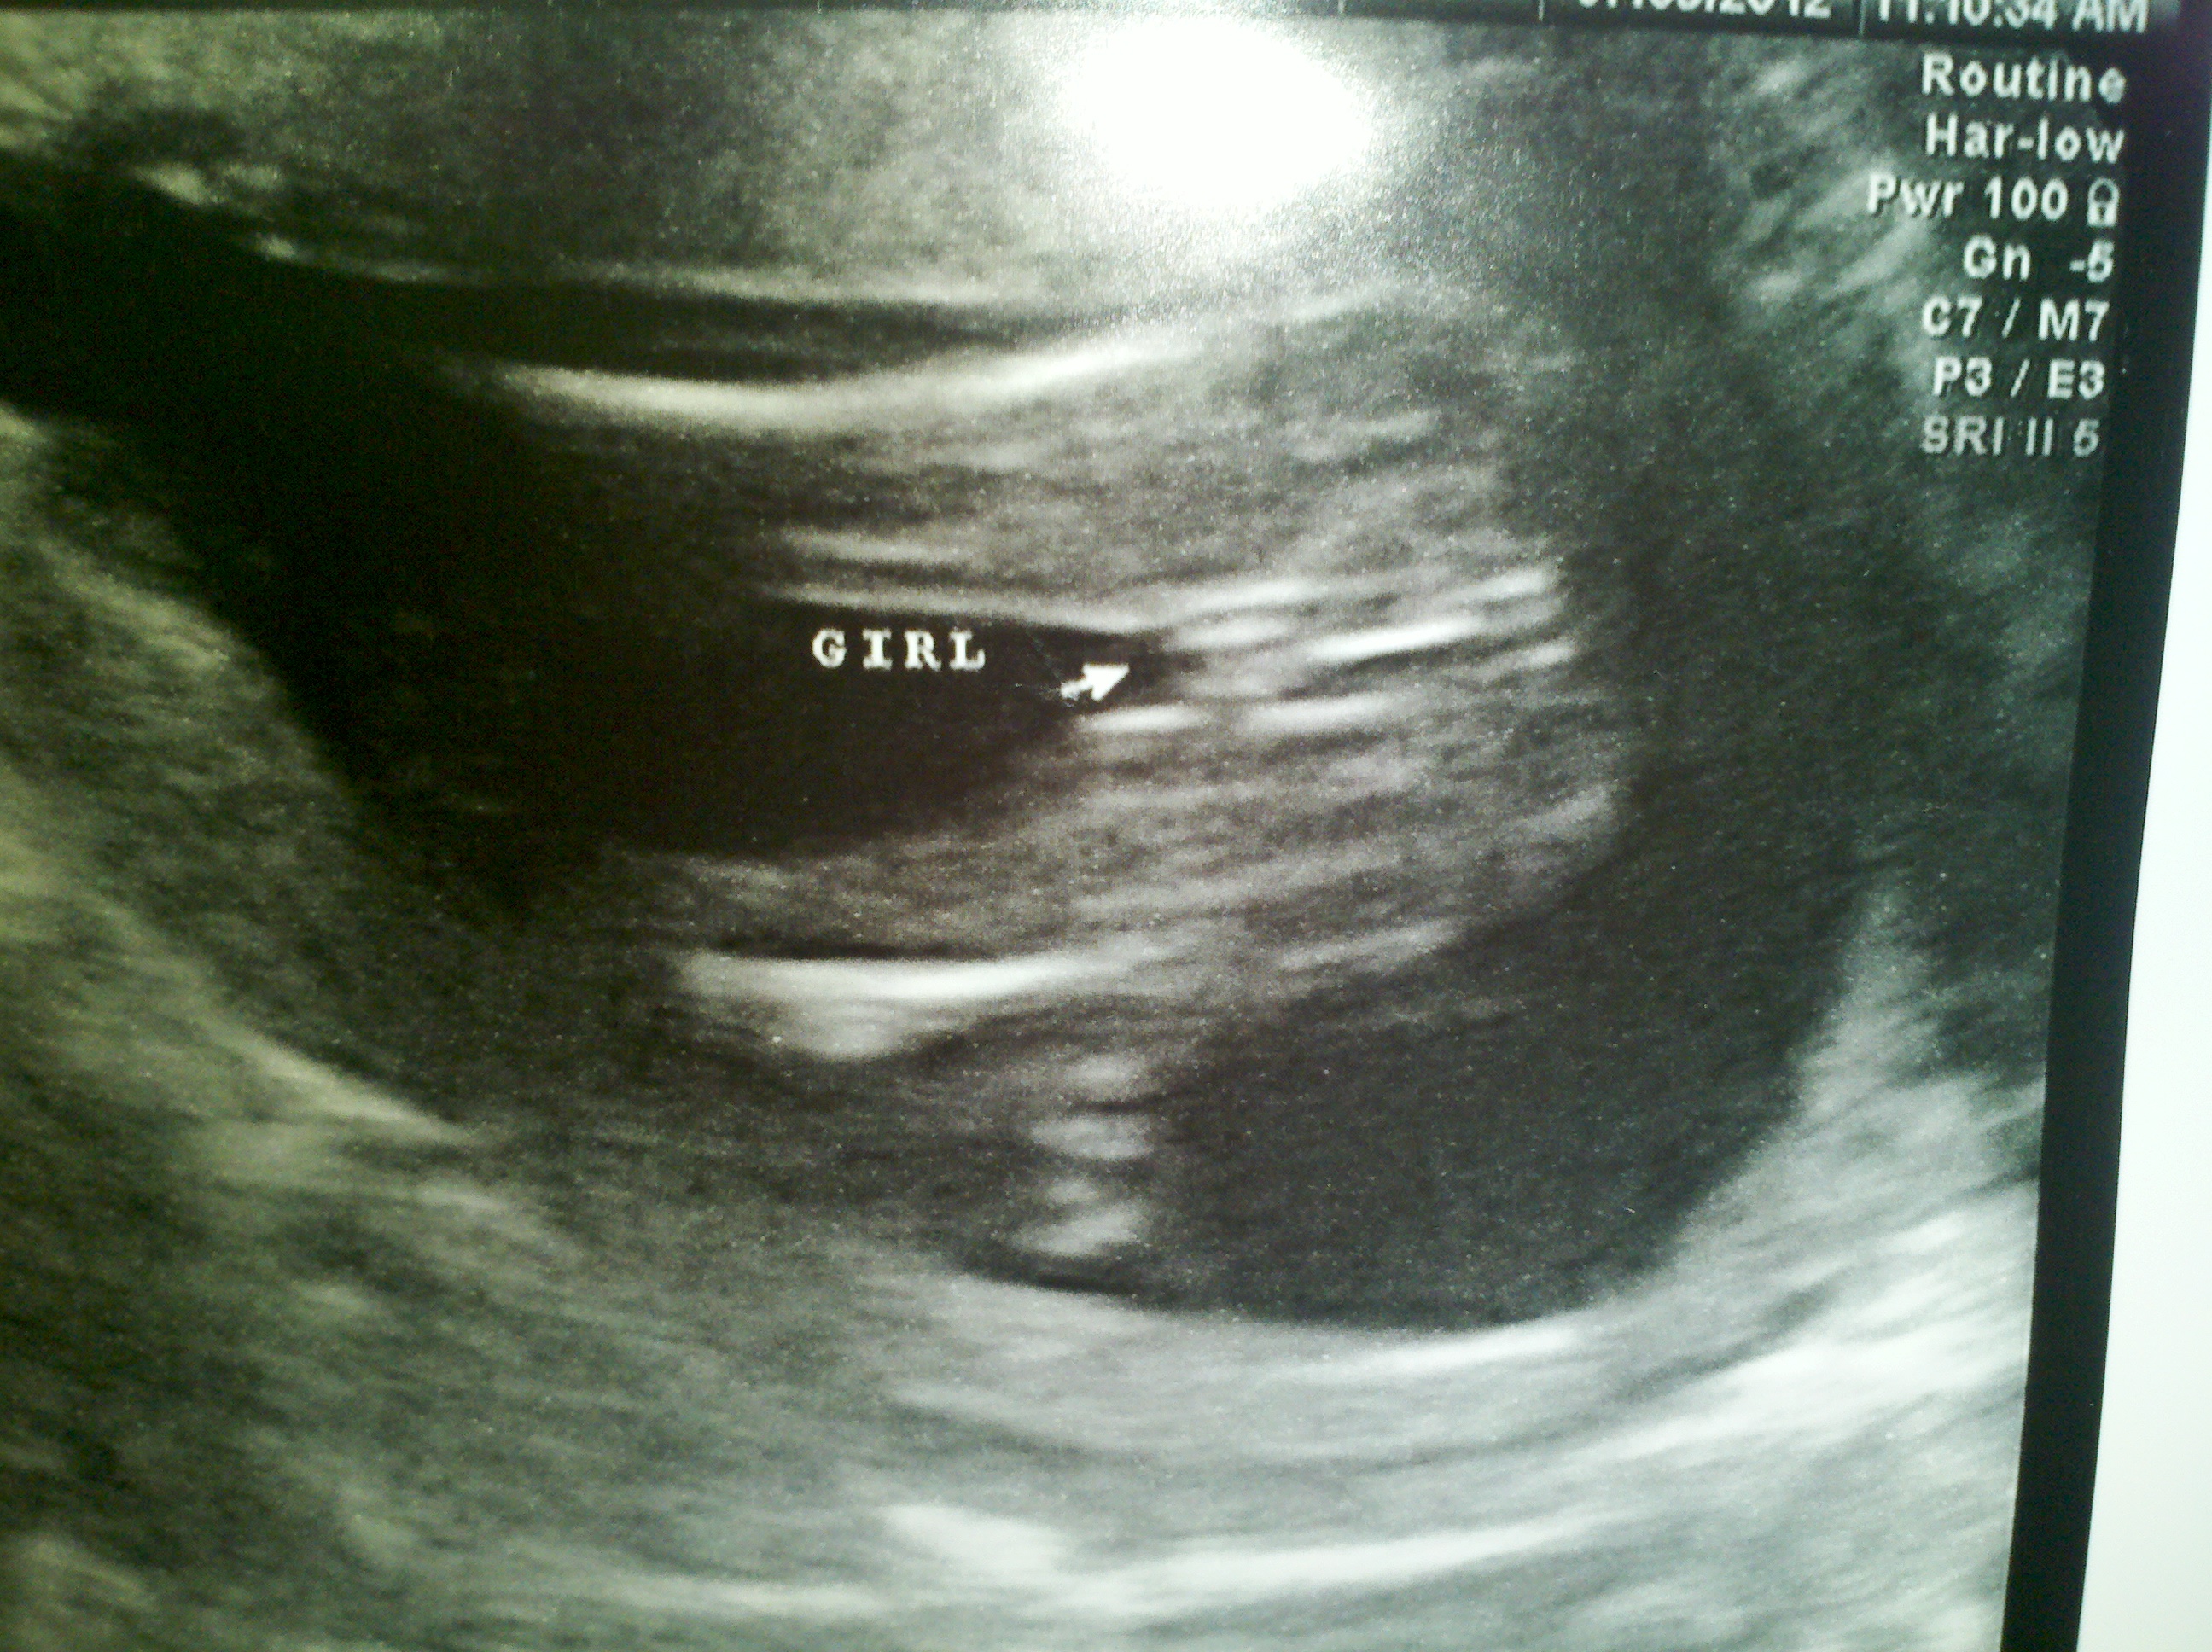

Its a GIRL!!!!!

Attachment 3538